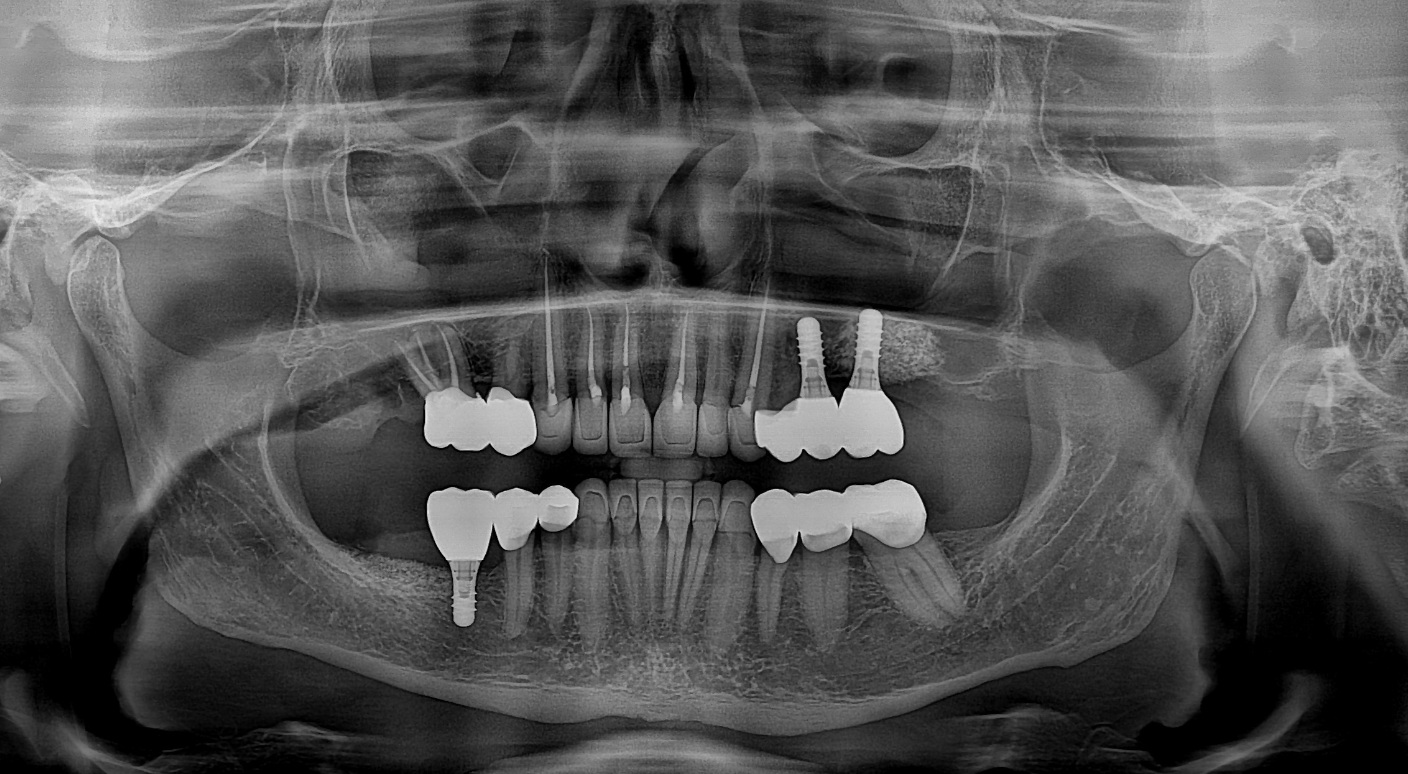

Általánosságban a szájsebészet a fogak, az állcsontok és a lágy részek (nyálmirigyek, íny, ajak) elváltozásainak, megbetegedéseinek gyógyításával foglalkozik, azonban manapság már sok átfedés tapasztalható a fogászat más ágazataival. Így a szájsebészet számos beavatkozást elvégez, például

- fogászati implantációt

Amennyiben gyökérkezelt fog esetén a gyökércsúcsnál gyulladás jelentkezik szájsebészeti megoldásként alkalmazható a gyökércsúcs csonkolása, azaz a gyökércsúcs rezekció, mely a fog megtartását célozza. A beavatkozás az ínyen való apró metszéssel történik, amelyen keresztül a gyulladásos csontterület, és a foggyökér csúcsa kerül eltávolításra.